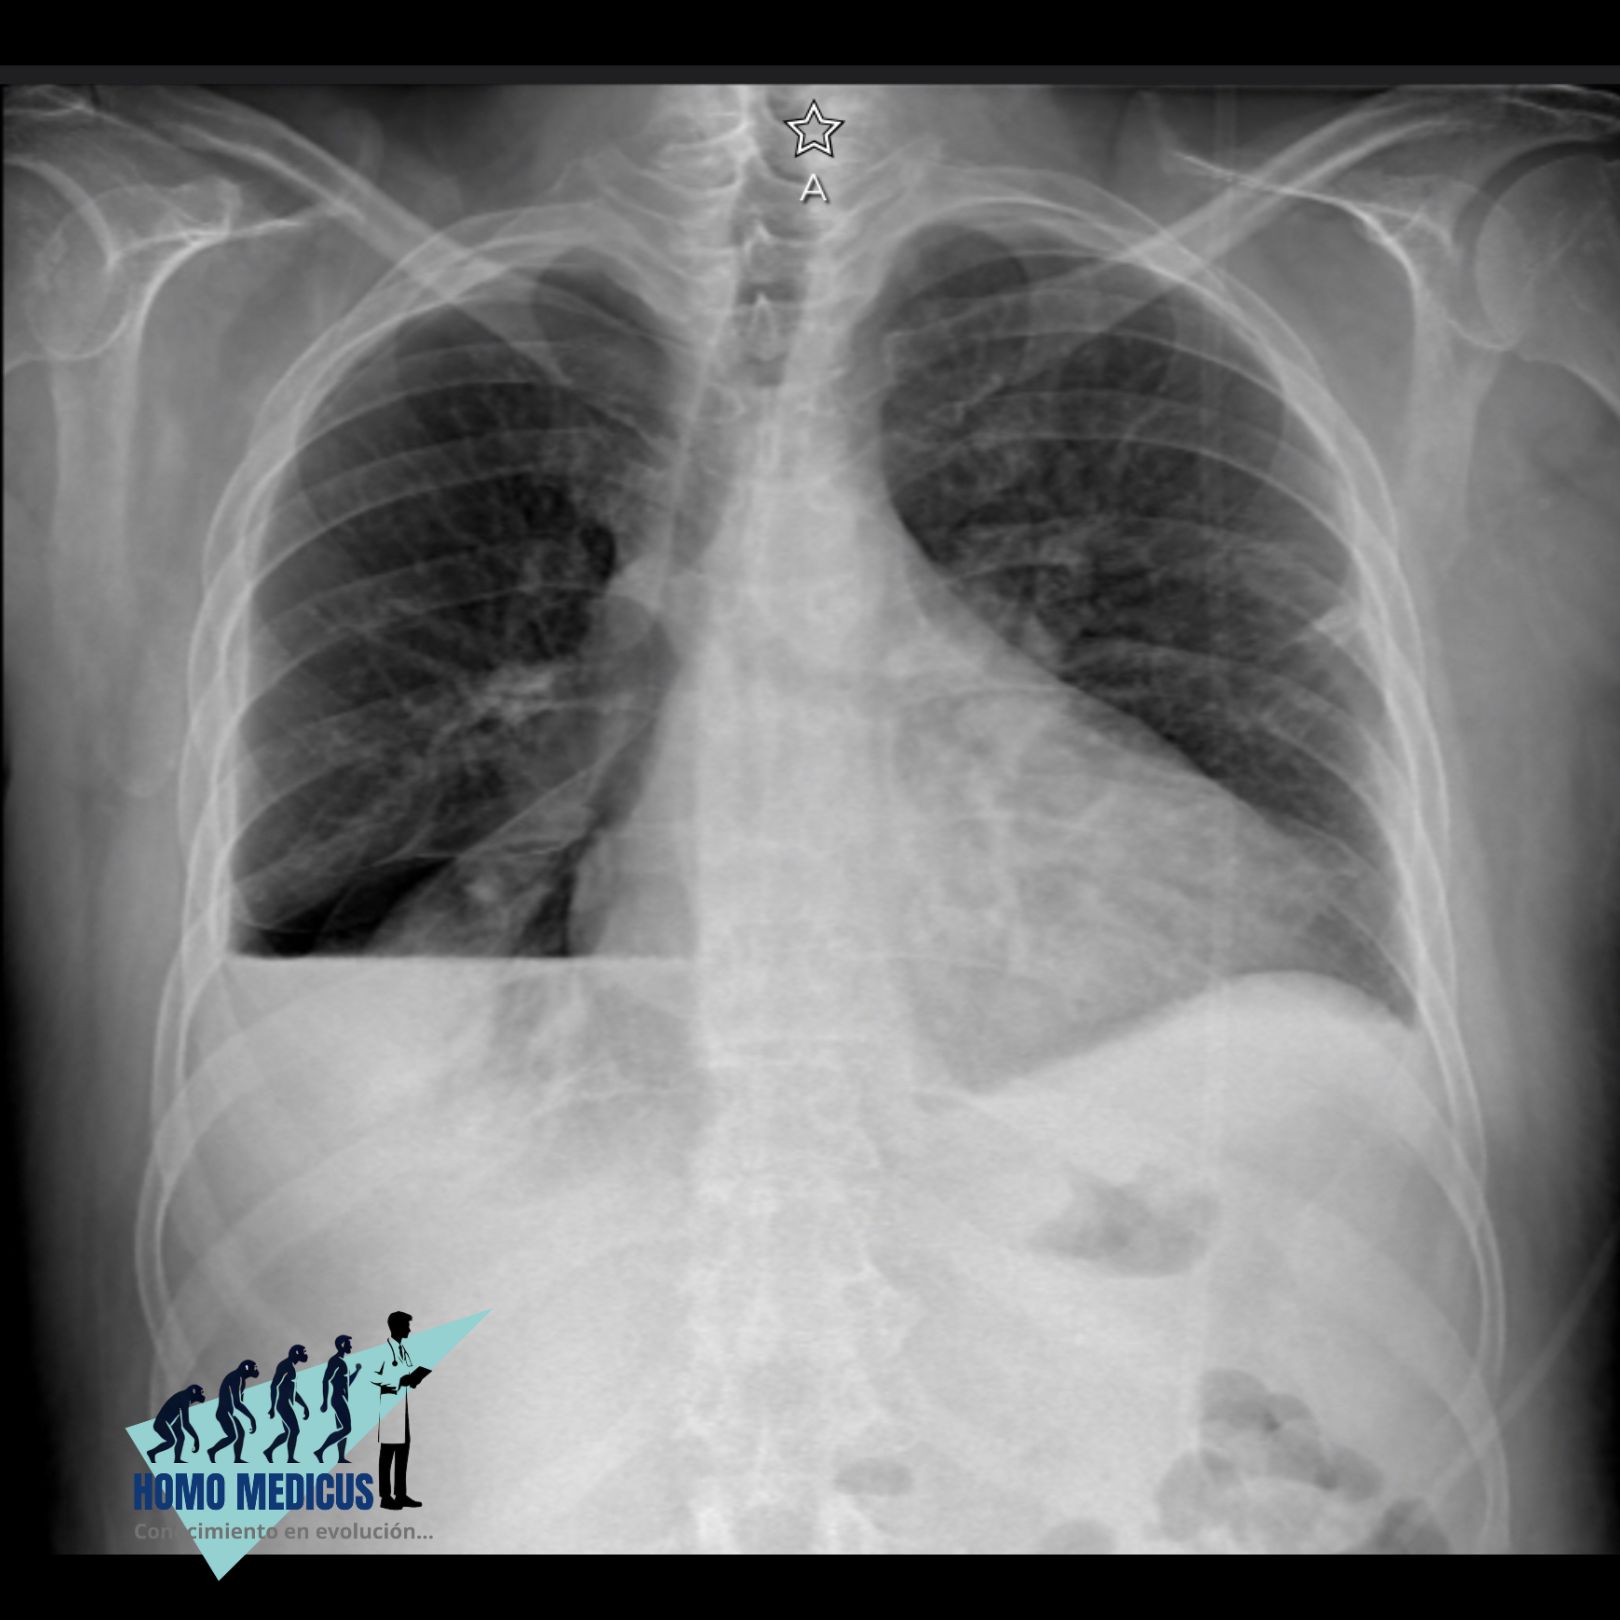

La evaluación por imágenes, particularmente a través de la radiografía de tórax, proporciona evidencia visual clave para el diagnóstico del derrame pleural. En una radiografía, el derrame se manifiesta como una opacidad en el área del pulmón, con un nivel horizontal de líquido visible en proyecciones de pie o una opacidad en la base del pulmón en proyecciones acostadas. Los signos radiográficos adicionales, como el desplazamiento del mediastino o la ampliación de la silueta cardiaca, pueden indicar la presencia de un derrame grande.